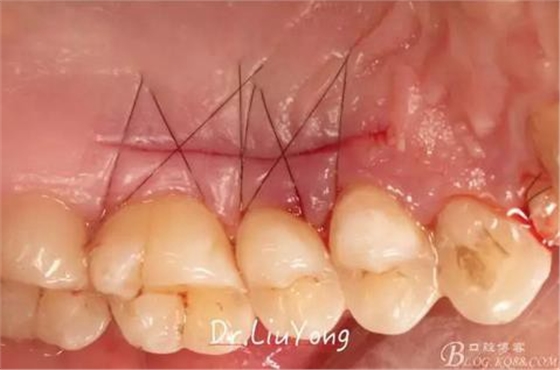

將結(jié)締組織瓣縫合固定于受區(qū),如上圖